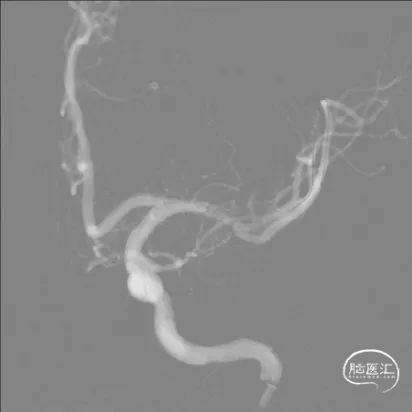

两条Avigo微导丝分别送入左大脑中动脉上下干。

导引导管到位,导丝通过病变

将赛诺神畅 颅内球囊扩张导管Neuro RX®2.00*15mm小心通过狭窄段。

球囊通过病变